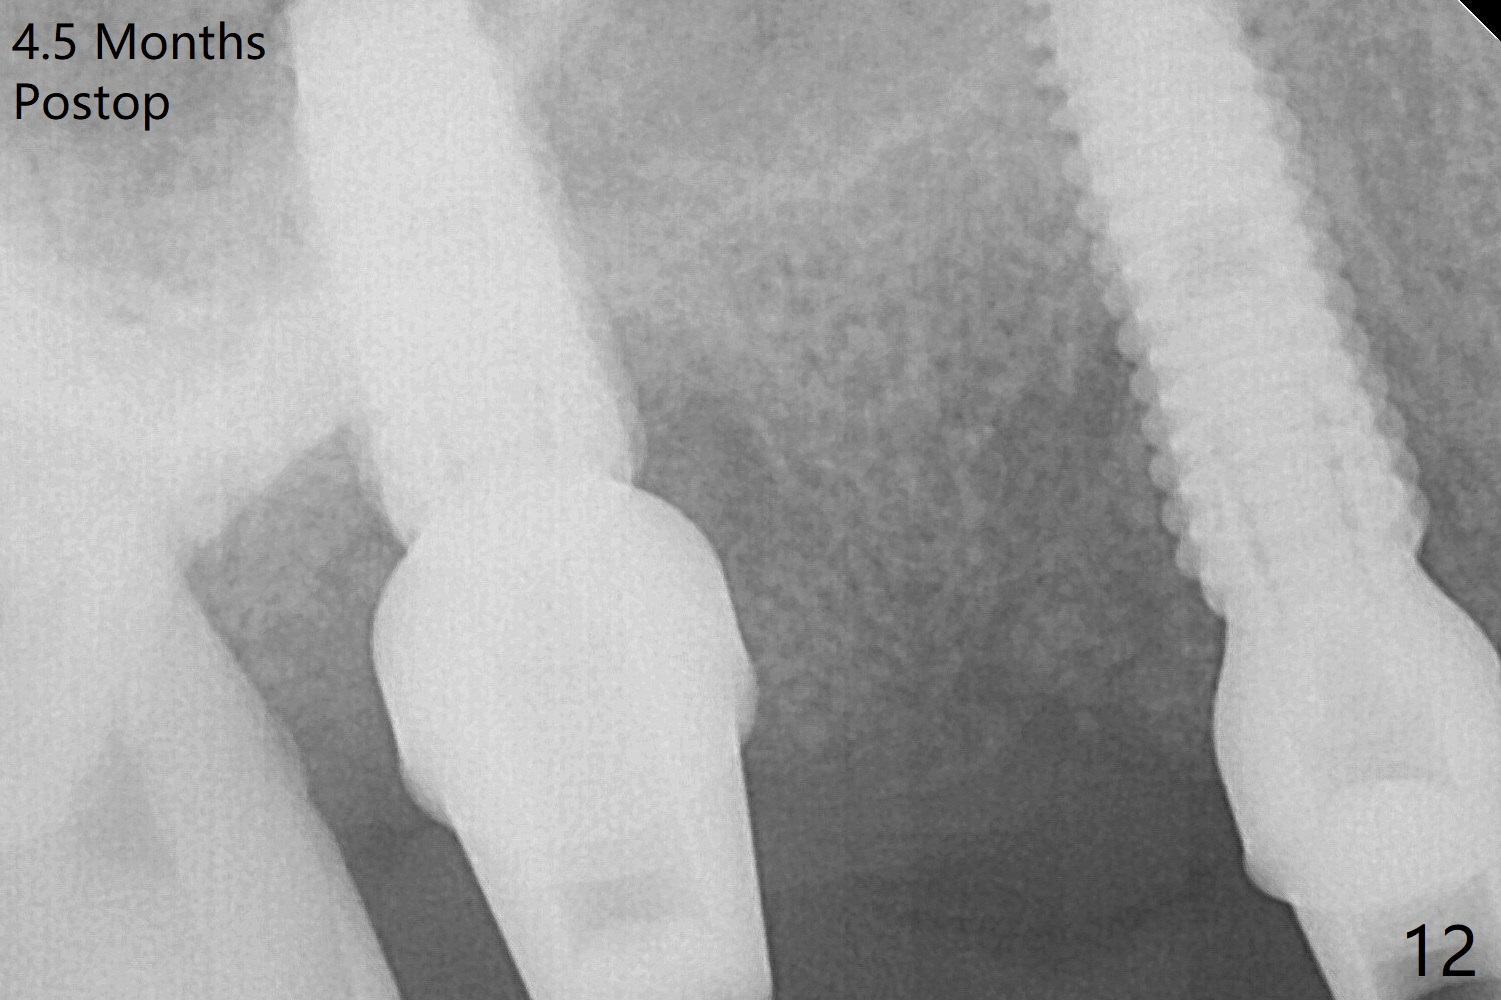

The implant at #5 is seated ~1 mm deeper (subcrestal mesially (^^); supracrestal distally (^)); allograft is placed around the implants prior to insertion of 6.5x7(5) and 5.5x4(5) mm abutments; last more allograft is added (Fig.9 *, 10). There is a large space buccally at #3 and 5, since the implants are placed palatally. Osteogen plug is placed buccally prior to placement of bone graft around the implants. The implants seem to have been osteointegrated 4.5 months postop (Fig.12). The gingiva is healthy around the implants without bone loss 3 months post cementation (Fig.13,14).